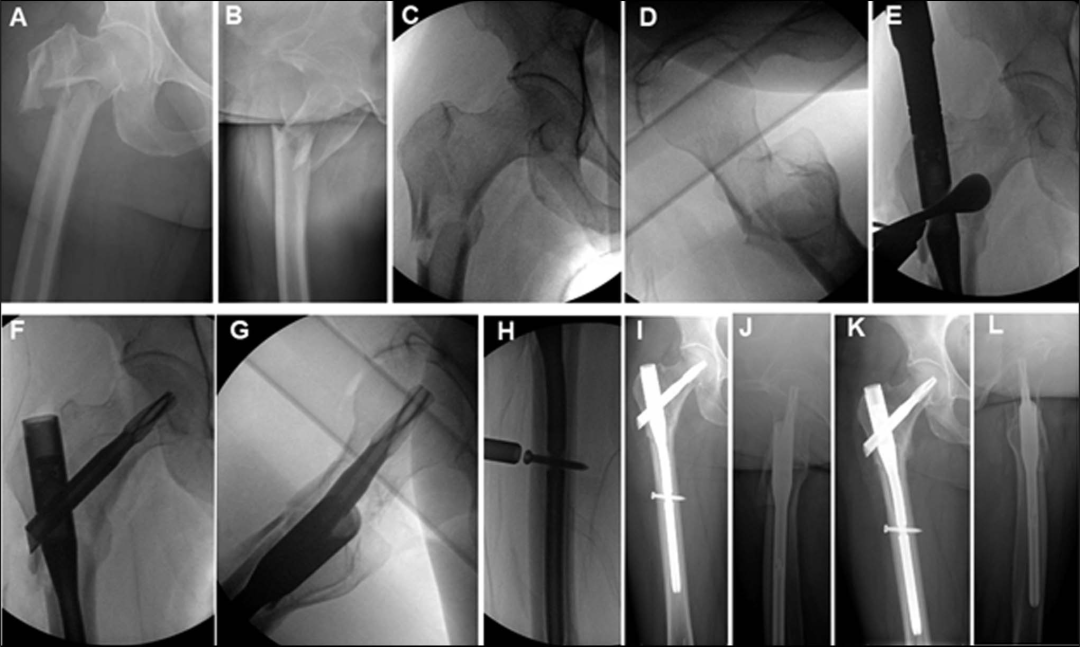

最常用的钉长是短钉(170~200mm)和长钉(300~480mm),(下图a短钉、c长钉)

短髓内钉手术时间短,远端锁定相对容易被广泛使用,短钉的缺点包括在髓腔宽或股骨近外侧皮质完整的患者中,可能发生钉子错位和随后的内翻塌陷,以及股骨近端骨干应力增加等。

长髓内钉更适合股骨髓腔宽、骨质疏松、病理性骨折、多次跌倒患者骨折、骨折伴近侧皮质缺损、转子间骨折延伸至小转子远端超过3cm。缺点,包括远端锁定困难、手术时间增加、扩孔需要增加、失血增加等。

。为了平衡短钉和长钉的优缺点,开发了中等长度的髓内钉(235和240mm):使用与短钉相同的远端锁定螺钉位置,但在锁定螺钉远端提供额外的钉子长度。

将锁定螺钉放置在动态位置(动态孔的中间),其在负重时允许骨折动态化。术后十二周的X射线图,显示骨折愈合进展和复位得以保持。